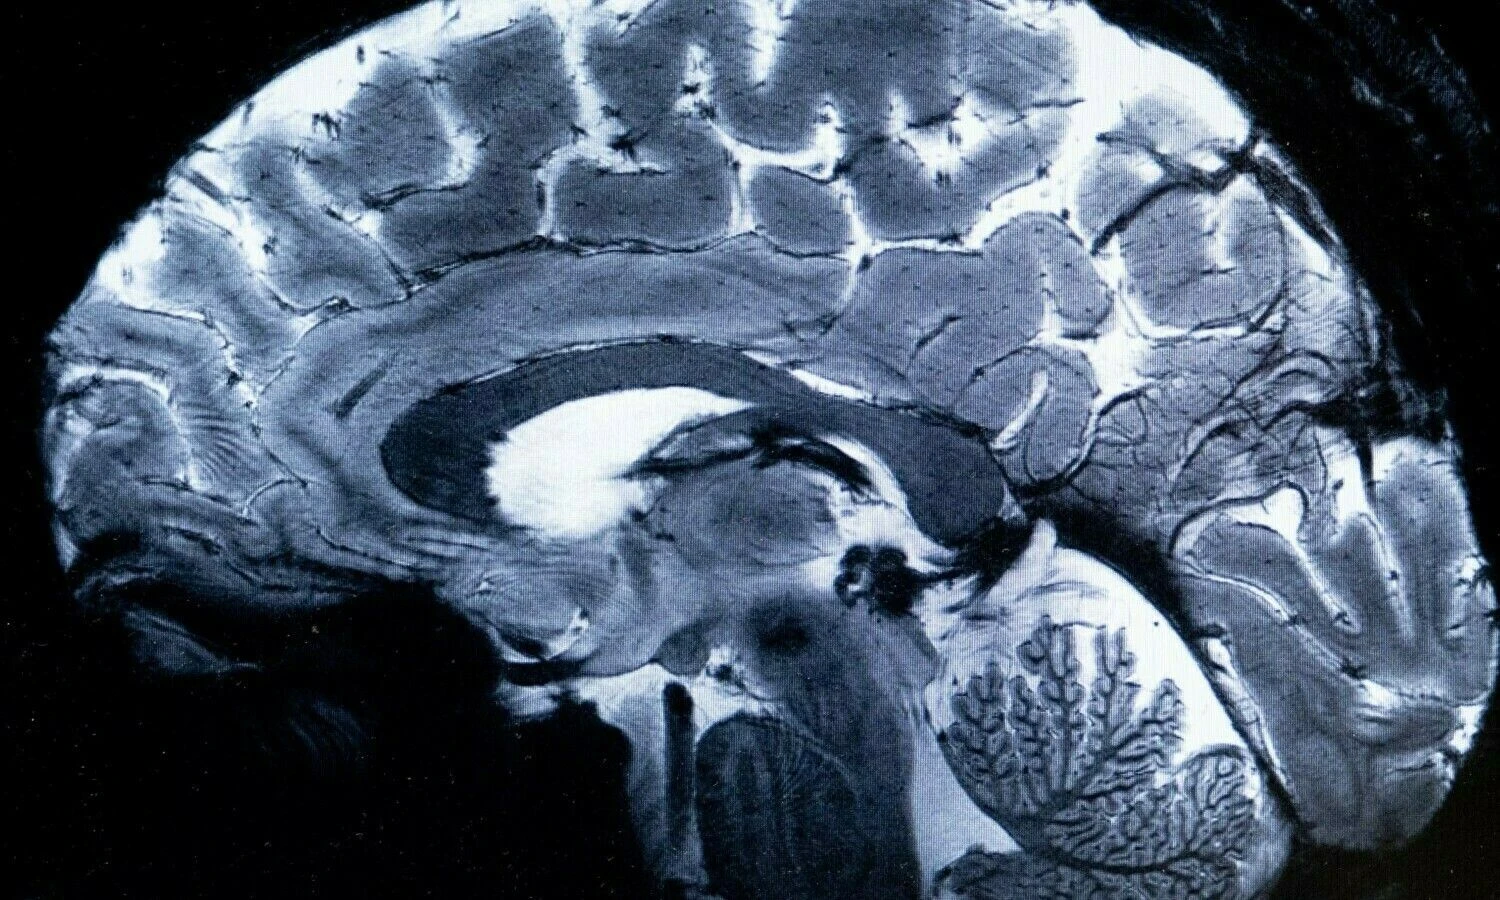

Magnetinio rezonanso tomografu padaryta smegenų nuotrauką. 2024 m. kovo 22 d. „Scanpix“ nuotr.